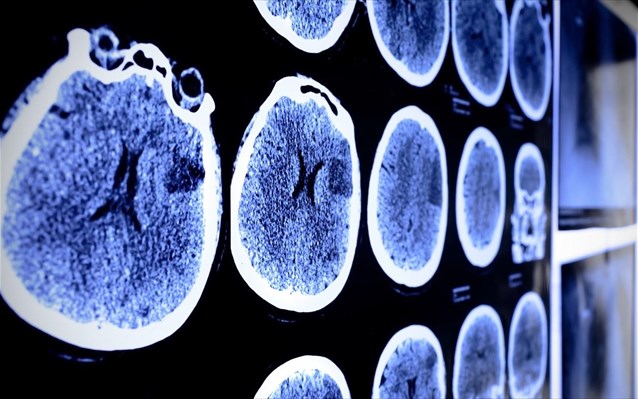

Αφετηρία της ημερίδας αποτελεί η συμπλήρωση τριών ετών λειτουργίας της Μονάδας Επεμβατικής Νευροακτινολογίας του Εργαστηρίου Ακτινολογίας του ΠΓΝ Λάρισας, η οποία διαδραματίζει καθοριστικό ρόλο στη διαχείριση ασθενών με Αγγειακό Εγκεφαλικό Επεισόδιο. Η μονάδα συμμετέχει ενεργά στη σύγχρονη θεραπευτική προσέγγιση της νόσου, προσφέροντας τη δυνατότητα της μηχανικής θρομβεκτομής, μιας μεθόδου που έχει αλλάξει τα δεδομένα στην αντιμετώπιση των οξέων αγγειακών εγκεφαλικών επεισοδίων.